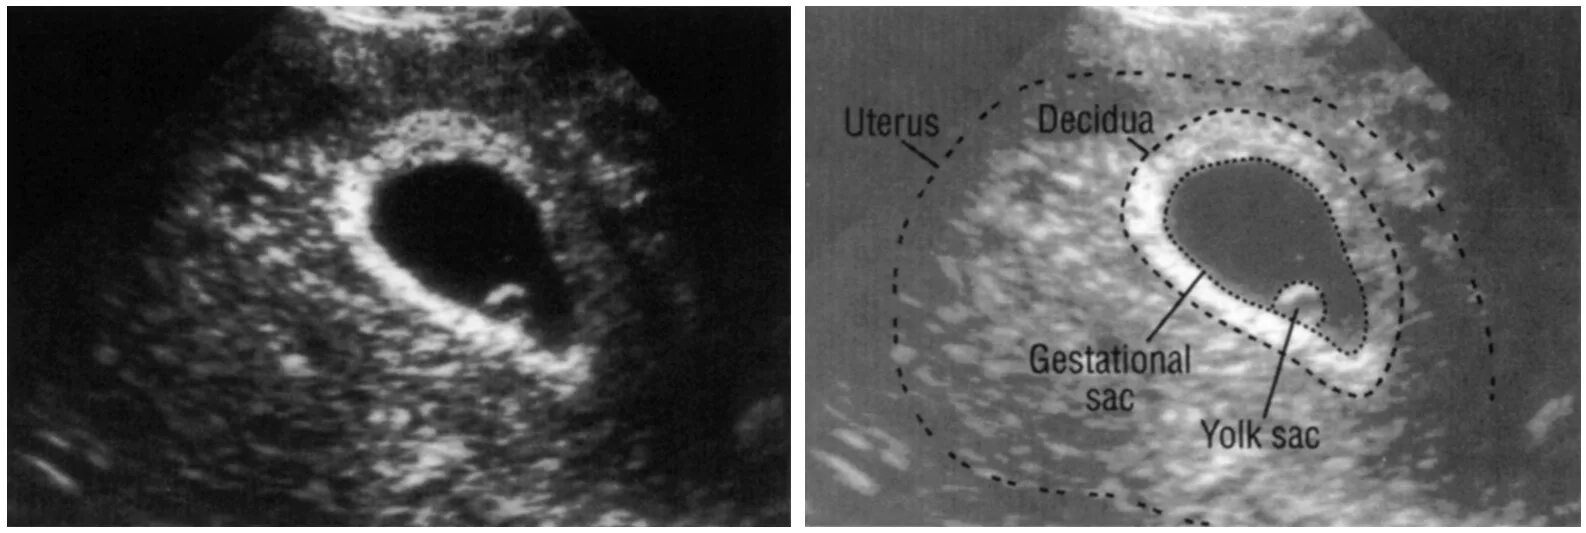

Узи 6 недель беременности желточный мешок. узи 8 недель беременности анэмбриония. плодное яйцо на 7 неделе беременности. плодное яйцо желточный мешок эмбрион.

Желточный мешок на узи 6 недель. анэмбриония с желточным мешком. плодное яйцо 5 недель на узи беременность 6. узи 6 недель беременности плодное яйцо на узи.

Желточный мешок на 5 неделе беременности на узи. плодное яйцо 16мм,эмбрион 6мм. плодное яйцо 7 мм желточный мешок 4мм. плодное яйцо на 5-6 неделе беременности.

Плодное яйцо 9 мм желточный мешок 3,6 мм. плодное яйцо 8 мм желточный мешок. плодное яйцо и желточный мешок. плодное яйцо 7.7мм желточный мешок 3.1.

Плодное яйцо 8 мм желточный мешок 4 мм на 7 неделе беременности. узи 6 недель беременности желточный мешок. деформированное плодное яйцо на 7 неделе беременности узи. узи 9 недель беременности желточный мешок.

Узи 5-6 недель плодное яйцо 12мм. плодное яйцо 9 мм желточный мешок 3,6 мм. плодное яйцо 8 мм желточный мешок 16 мм. плодное яйцо 8 мм желточный мешок 3 мм.